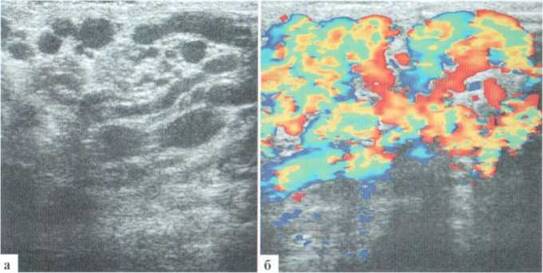

Исследования сразу начинается с ортостатической пробы. Датчик устанавливается слева у корня мошонки, располагается в длину, по направлению к дну мошонки, фиксируется диаметр вен в ортоетазе (рис. 3.1, а) и при допплеровском режиме — наличие ретроградного кровотока (рис. 3.1, б) в венах. Собственно эхографическая оценка яичек на этом этапе исследования не проводится.

Рис. 3.1. Исследование в оротостазе

Проводится проба Вальсальвы: датчик устанавливается слева у корня мошонки, включается режим цветового доплера. По просьбе врача подросток последовательно делает глубокий вдох и затем напрягает живот, в течение этого времени оценивается сосудистый рисунок в проекции гроздьевидного сплетения (рис. 3.4). При подозрении на варикоцеле справа проба повторяется справа. При положительной пробе Вальсальвы уже на вдохе определяются реверс кровотока и значительное усиление сосудистого рисунка, которое достигает максимума во время напряжения передней брюшной стенки.

Рис. 3.4. Проба Вальсальвы:

а — исходное состояния; б — глубокий вдох — смена направления кровотока (стрелка); в — напряжение передней брюшной стенки резкое нарастание интенсивности окрашивания сосудов соответственно увеличению скорости кровотока